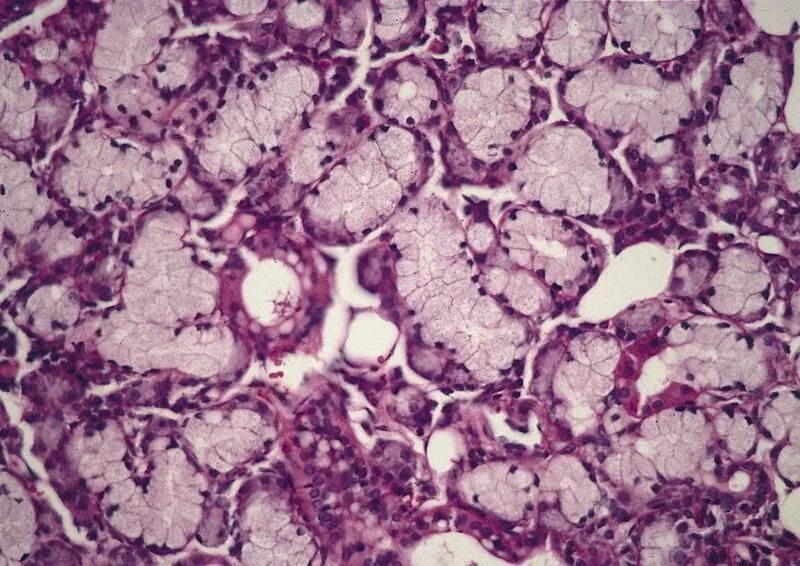

Подъязычной железы гистология